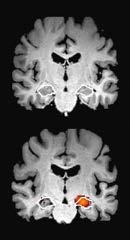

Bislang ist noch keine Heilung der Erkrankung möglich, erstmals können nun aber spezielle Medikamente die Plaques im Gehirn von Alzheimer-Erkrankten auflösen. Die Namen dieser Medikamente klingen kompliziert und sehr ähnlich: Lecanemab und Donanemab. Das „mab“ am Ende steht für „Monoclonal Antibody“ – die Präparate bestehen also aus Antikörpern. Sie sollen krankhafte Eiweiß-Verklumpungen (Plaques) bekämpfen, das sogenannte Beta-Amyloid. In einer 18 -monatigen Studie schnitten leicht erkrankte Patientinnen und Patienten, die den jeweiligen Wirkstoff erhielten, in Gedächtnistests messbar besser ab. Die Erkrankung schritt in der Lecanemab-Gruppe um 27 Prozent langsamer als in der Kontrollgruppe voran. Unter Donanemab verzeichnete man sogar eine Verlangsamung von 35 Prozent. Die Zahlen klingen erst mal beeindruckend, in der Realität bedeutet es jedoch eine Verzögerung des Verlaufes um höchstens ein paar Monate. Für viele Betroffene und Angehörige kann dies allerdings auch schon ein großer Fortschritt sein, es könnte weitere Lebensjahre mit geringerer Einschränkung bedeuten. Vor allem in der Frühphase der Erkrankung können die Patien-

ten von der Therapie profitieren, im späteren Stadium ist das Gehirn schon zu sehr beschädigt. Lecanemab wurde im Sommer 2023 in den USA durch die FDA (Food and Drug Administration) zugelassen, die Entscheidung der Europäischen Arzneimittel-Agentur wird voraussichtlich im Laufe des Jahres 2024 erfolgen. Auch für Donanemab wurde die FDA-Zulassung beantragt.

Die Therapie wird für alle Beteiligten sehr aufwendig sein. Wie der genaue Therapieprozess laufen wird, ist zum jetzigen Zeitpunkt noch nicht abschließend geklärt. Aktuell werden noch die entsprechenden Voraussetzungen in den verschiedenen Zentren und Arztpraxen geschaffen. Zu Beginn werden mindestens eine MRT-Untersuchung des Gehirns, eine Nervenwasseruntersuchung und neuropsychologische Tests zur Erfassung der Gedächtniseinschränkungen benötigt. Während der Behandlung muss eine engmaschige Betreuung erfolgen, unter anderem mit weiteren regelmäßigen MRT-Untersuchungen zur Verlaufskontrolle, vor allem zu Beginn der Therapie. Die Behandlung wird über mehrere

Monate andauern, die genaue Dauer ist aktuell noch gar nicht bekannt. Es ist auch nicht klar, welche Auswirkungen die Therapien auf lange Sicht haben, das muss noch beobachtet und ausgewertet werden.

Wie jede Medikation kann auch diese Nebenwirkungen verursachen. Es kann zu Hirnschwellungen kommen, auch wurden kleinere Hirnblutungen nachgewiesen, welche jedoch in den meisten Fällen symptomlos verliefen. Das bedeutet jedoch zugleich ein erhöhtes Risiko für eine stärkere Hirnblutung. Es müssen daher Betroffene ausgeschlossen werden, die ein erhöhtes Blutungsrisiko haben, zum Beispiel Menschen mit Blutgerinnungsstörungen oder solche, die Gerinnungshemmer einnehmen. Unter dem Strich kommt damit am Ende höchstens jeder zehnte Alzheimer-Erkrankte überhaupt in Frage.